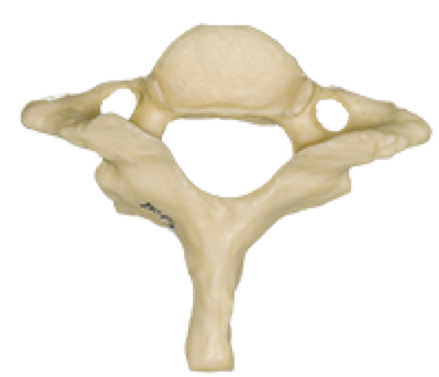

what vertebrae

C7